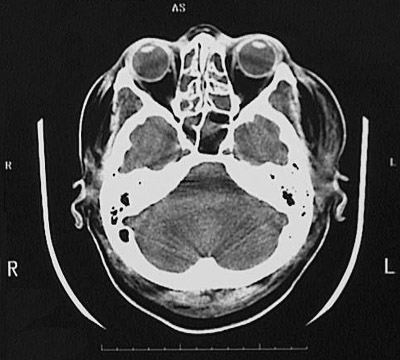

This is a normal head CT scan demonstrating the base of skull with the globe of eye and lens of eye and frontal bone and ethmoid sinus and sphenoid sinus and temporal lobe and mastoid air cells and pons and cerebellar hemisphere.